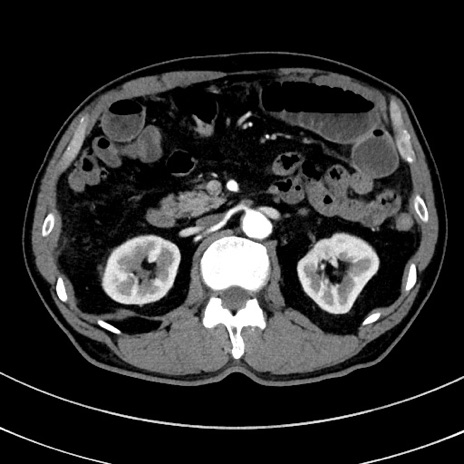

症例8(横断像)

【症例】 60歳代男性

【主訴】 黒色吐物

【現病歴】 4日前から嘔気自覚、2日前の朝食後にも嘔気あり、自分で手で嘔吐反射起こし嘔吐したところ血が混ざっていたため受診。

【既往歴】 5年前汎発性腹膜炎を伴う急性虫垂炎で手術、高血圧、前立腺肥大症、高脂血症

【身体所見】 腹部正中に手術癩痕あり 腹部平坦・軟圧痛なし膨満感あり

【データ】WBC 8400、CRP 4.54